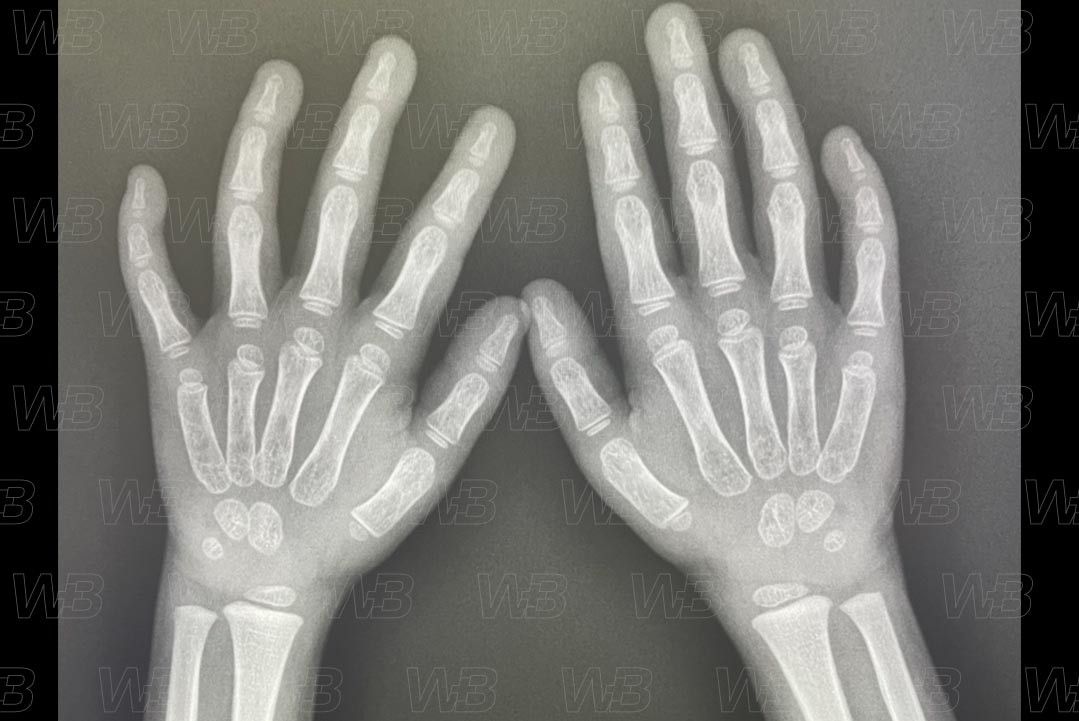

RADIOGRAFIA MÃOS E PUNHOS

Feminino

2 anos e 6 meses:

• Epífise das falange proximal do polegar corresponde a mais da metade da metáfise;

• Epífise distal do segundo dedo e média do qui dedo.